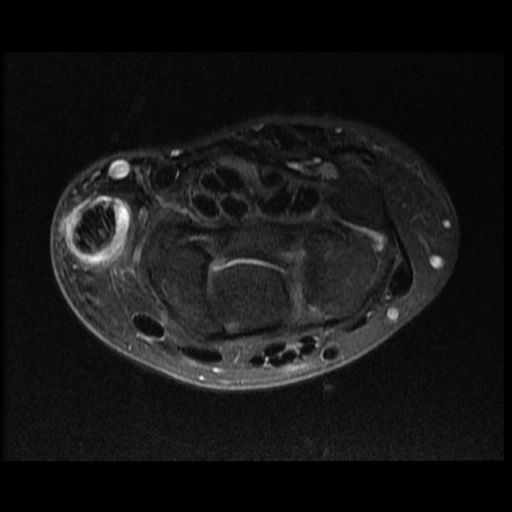

Viêm bao gân De Quervain (De Quervain tenosynovitis)

16/03/2026